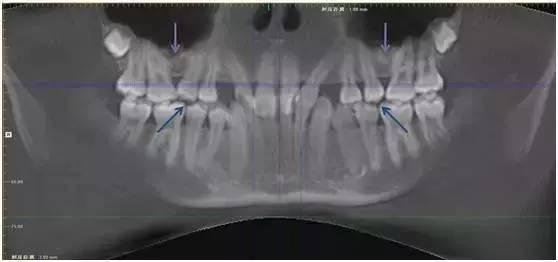

局部解剖异常

局部解剖异常造成牙齿萌出受限在临床上比较少见,但治疗难度比较大,而且往往需要多学科配合。

下面这位患者就是因为上颌窦气化过于充分,窦底接近牙槽基骨的顶端(如图紫色箭头处),造成双尖牙区域牙槽基骨骨量不足,第二双尖牙无法正常萌出(如图蓝色箭头处)。

这种情况即使进行正畸治疗,也会因为局部骨量不足,出现第二双尖牙无法牵引到位或根周骨量不足的风险。

因此患者接受了上颌窦底提升植骨术,一年后牙槽基骨成骨充分,牙齿自行正位萌出。此时再进行正畸治疗,难度和风险将大大减小。

图:上颌窦底提升植骨术后一年